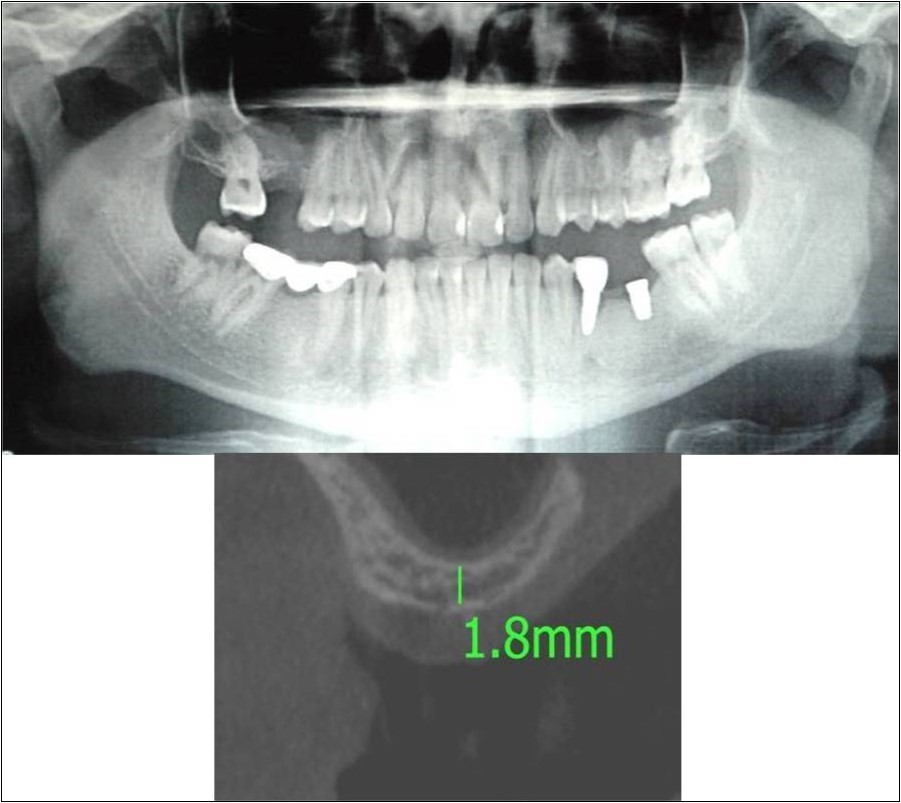

Clinical and Radiological Assessment:

3.Height of available bone- 1.8mm;

4.Transverse thickness of available bone (CBCT evaluation)- 6.2mm;

Treatment:

Patient underwent the procedure of direct sinus elevation using sinus lateral approach kit. After crestal and vertical release incisions, muco-periosteal flap was raised to expose the buttress region. A bony window of 1cm diameter was created; sinus lining identified and elevated up to receive calcium phosphosilicate as graft material and closure was achieved under local anaesthesia and strict aseptic protocols. Implant placement was planned to be carried-out after a period of 6 months to allow for the consolidation for graft and naive bone formation. At the end of 6 months, a repeat CBCT scan was advised to evaluate the increase in bone height. (Figure 17a,b, pre-treatment; Figure 18a,b, post-treatment)

Figure 17.a,b. Pre-treatment OPG and cross section of CBCT showing residual alveolar bone height for Case No.6;